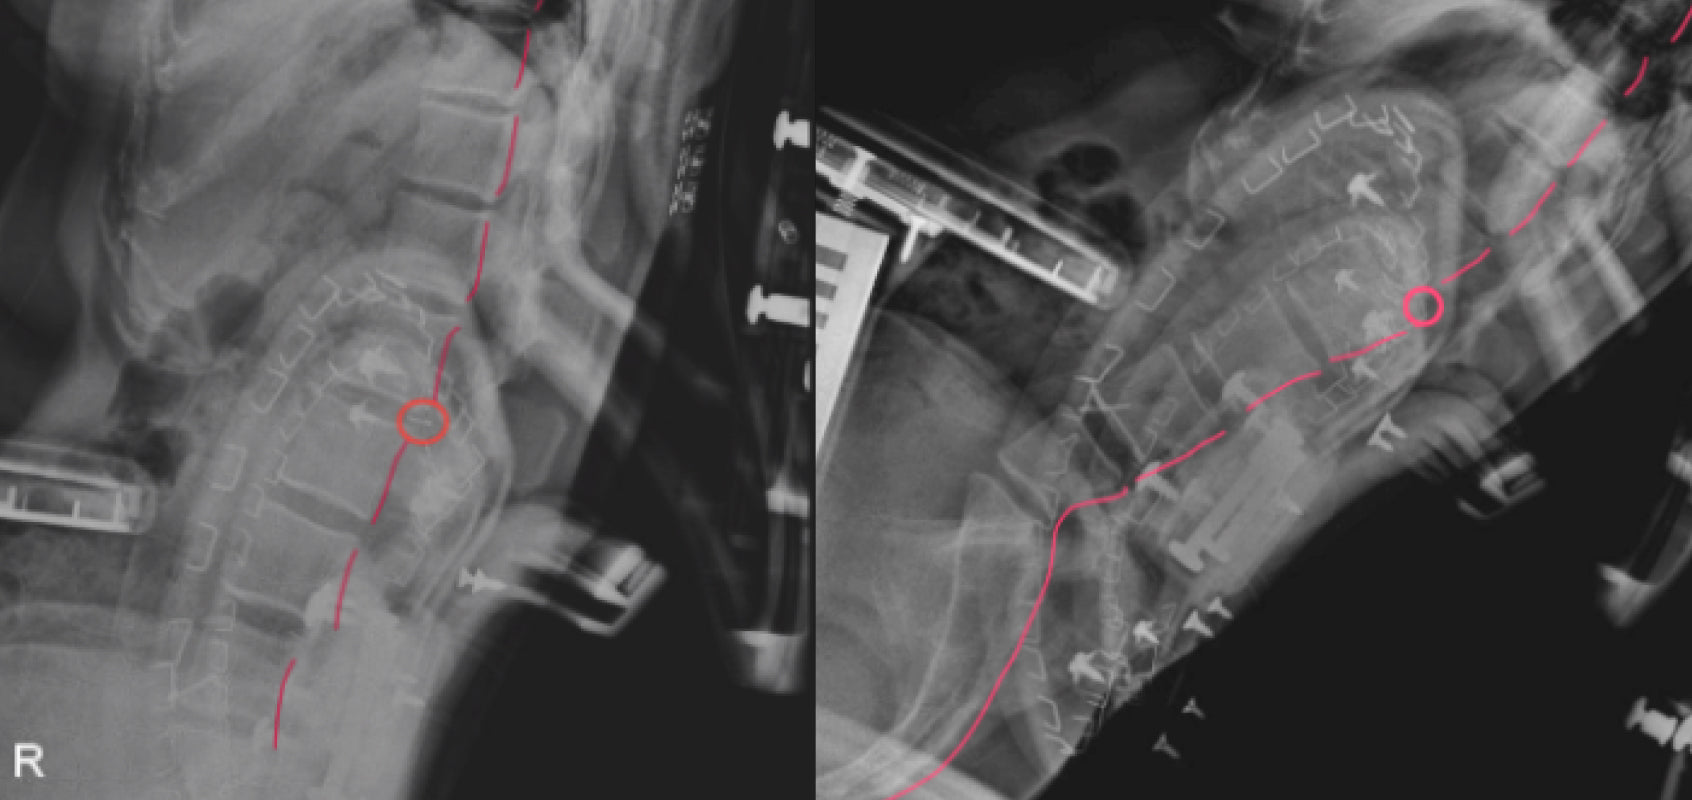

We’ve also found that chairs with pronounced lumbar protrusions can actually disrupt the spine’s natural curve, as shown in X-ray imaging. This leads to unnatural breaks in spinal alignment and increases pressure on specific segments of the spine.

*Source: LiberNovo Internal Laboratory